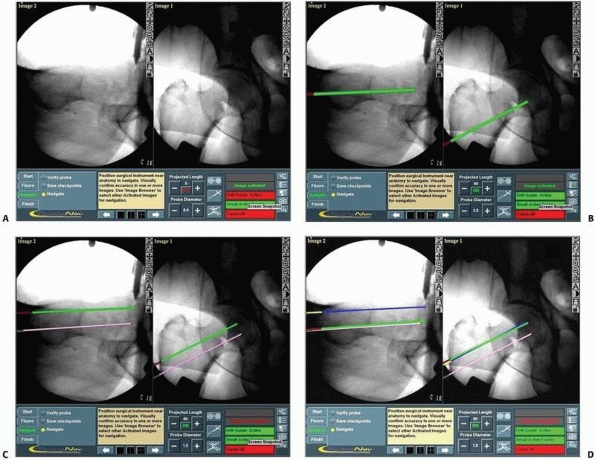

fluoroscopic images, the surgeon can accurately determine the entry

can be calculated (Fig. 17-12). After satisfactory virtual alignment and length have been achieved, the conventional

than one screw (Figs. 17-13 and 17-14).

![]() |

|

FIGURE 17-12 Cannulated screws. A. Anteroposterior and lateral views of a reduced intracapsular fracture of the femoral neck displayed on the computer’s screen. B-D. Insertion of the three guidewires without additional radiation. (continues)